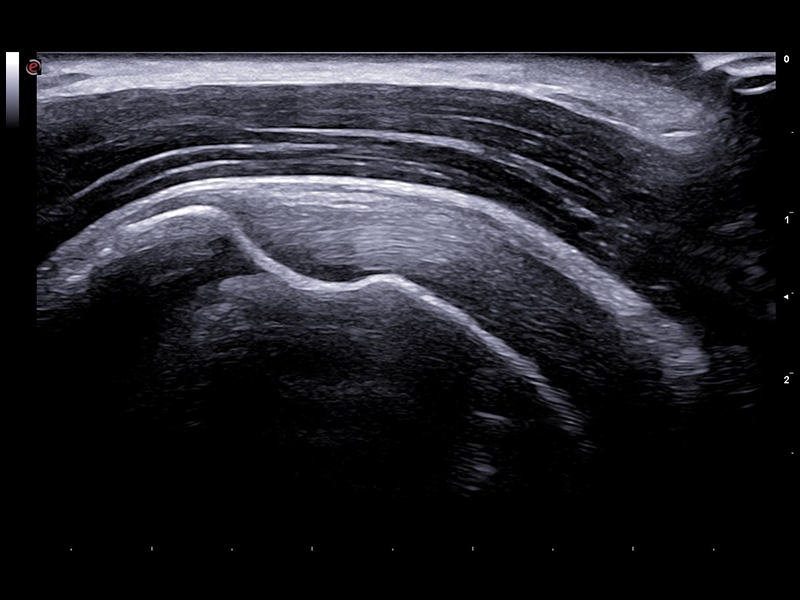

The use of our latest Very-High Frequency Hockey Stick probe, also operating up to 25MHz, delivers outstanding spatial resolution while facilitating needle access to perform accurate interventional gestures with millimetric precision.

• Frequency range: 6-25 MHz

These arrays, enabling to operate up to 25 MHz, provide outstanding image quality for very superficial scans, such as fingers, elbows, and wrists and, for example, allow accurate evaluation of the hyaline cartilage of the metacarpal head.